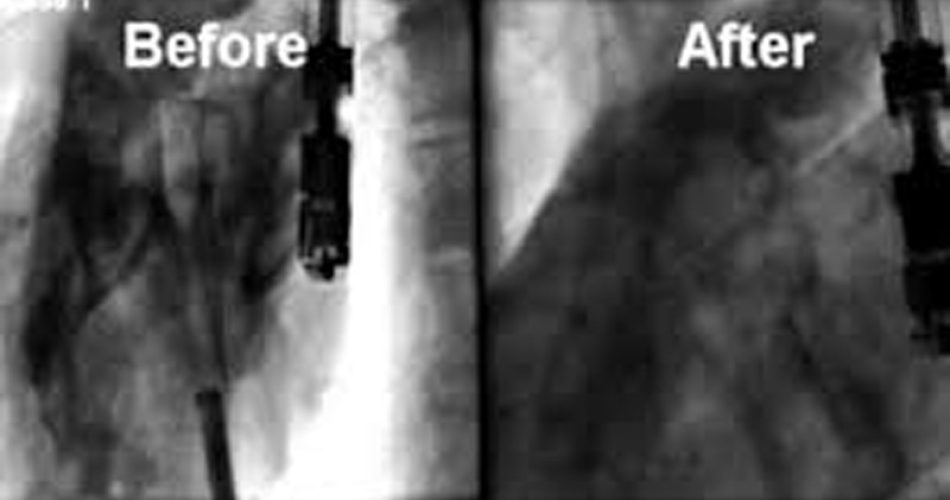

Si tratta di un filo di sutura che entra per via percutanea attraverso la vena della gamba e viaggia verso il cuore sotto la guida di fluoroscopia (X-ray) per chiudere il tunnel. L’efficacia della procedura per la chiusura del PFO è paragonabile a quella dell’intervento chirurgico ma con minori complicazioni e minore ospedalizzazione. L’intervento può richiedere meno di 20 minuti. L’idea di poter chiudere a distanza mediante un semplice filo chirurgico un buco dentro il cuore battente senza lasciare alcun dispositivo al suo interno è sicuramente vincente e costituisce un modo assolutamente rivoluzionario di approcciare la problematica del PFO e, probabilmente nel prossimo futuro, anche di altre patologie cardiache.

Esistono diverse soluzioni per la chiusura del PFO e quella mediante dispositivi occludenti, da circa 20 anni, pur dimostratasi una tecnica sicura ed efficace con un basso rischio di complicazioni, è stata completamente rivoluzionata dall’introduzione di una tecnica innovativa, per via periferica, mediante sutura diretta a cuore battente, con anestesia locale e quindi a paziente sveglio.